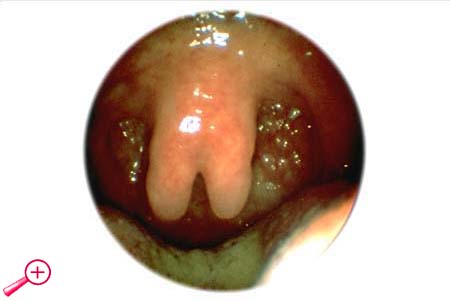

2.1. Formen der Gaumenspalte

Die Ausdehnung der Gaumenspalte kann sehr unterschiedlich sein und von der einfachen Uvula bifida...